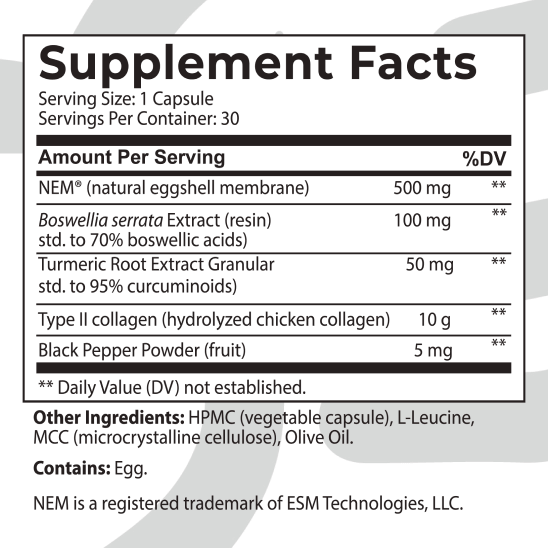

INGREDIENTS:

NEM® EGGSHELL MEMBRANE

NEM® is a clinically proven trademarked ingredient containing natural glycosaminoglycans and proteins critical for maintaining healthy joints. Recent studies show it significantly reduces inflammation, damage to cartilage and tissues, and bone decay and improves periosteal bone formation.* A Canadian clinical study showed statistically significant reductions in knee stiffness and soreness at 10, 30, and 60 days.* Researchers also observed rapid recovery from exercise-induced stiffness and discomfort with 500mg of NEM® daily.*

BOSWELLIA SERRATA

TURMERIC ROOT EXTRACT (95% CURCUMINOIDS)

Evidence shows the bioactive compound in Turmeric, curcumin, profoundly reduces joint discomfort, swelling, and stiffness. It helps block inflammatory molecules and enzymes from overactivity, alleviating the attack on your joints and giving your body a chance to rebuild and repair.*

COLLAGEN TYPE II (FROM CHICKEN STERNUM CARTILAGE)

Research shows type II collagen significantly improves joint discomfort, walking function, mobility, and quality of life.* Collagen diminishes immune T cells, which leads to swelling and stiffness.

BLACK PEPPER FRUIT

Piperine is a component of black pepper which has tremendous benefits in easing inflammation and joint discomfort. It also boosts Turmeric absorption, promoting maximum effectiveness.*

These powerful natural ingredients are clinically and scientifically proven to target specific joint functions and inflammation and improve functional joint health and overall well-being.

Check out our NEW Nation Health MD Joint Complex HERO’s ingredient lineup…

NEM® Eggshell Membrane: Researchers were thrilled with its results that they stated analysis demonstrated that NEM® supplementation could considerably help a significant number of patients. “NEM® has potential for a new natural therapeutic for joint and connective tissue disorders.”* Studies showed participants saw results in as little as 7-10 days and dramatic improvements with long-term use.

Boswellia, Turmeric, and Pepper: When combined, researchers found significant improvements in the ability to perform daily activities. They dramatically reduced stiffness and soreness by 37-39% and function scores by 30%. Boswellia considerably improves knee joint function by dramatically reducing immune markers, swelling, and discomfort, allowing better freedom of movement.***

Collagen Type II: A major cause of joint swelling, discomfort, and disease is from overactive immune markers called T cells that react with an antigen in your joint capsule. These T cells trigger immune cytokines that stimulate synovial fibroblasts (bone-producing cells) and chondrocytes (cartilage cells) to secrete enzymes. These enzymes degrade peptidoglycan and cartilage, which leads to bone destruction. Immune markers also stimulate bone breakdown, promoting nitric oxide synthase (iNOS), further tearing down bone.* Type II Collagen is an enemy of this process. Studies showed remission of disease in patients supplementing with Type II Collagen.*

EFFECTIVE INGREDIENTS: NEM® Eggshell Membrane, Boswellia serrata Resin Extract (70% boswellic acids), Turmeric Root Extract (95% curcuminoids), Collagen Type II (from chicken sternum cartilage), Black Pepper Fruit.

CONTAINS: Egg.

DIRECTIONS: As a dietary supplement, adults take one (1) capsule daily. For best results, take with 6-8 fl oz of water or as directed by a healthcare professional. Store in a cool, dry place.

SAFETY FACTS: Do not exceed recommended dose. Pregnant or nursing mothers, children under the age of 18, and individuals with a known medical condition should consult a physician before using this or any dietary supplement.

WHAT ARE THE EFFECTIVE INGREDIENTS IN NATION HEALTH MD JOINT COMPLEX?

WHAT ARE THE EXPECTED EFFECTS OF EACH INGREDIENT IN NATION HEALTH MD JOINT COMPLEX?

NEM® Eggshell Membrane – NEM® is a clinically proven trademarked ingredient containing natural glycosaminoglycans and proteins critical for maintaining healthy joints. Recent studies show it significantly reduces inflammation, damage to cartilage and tissues, and bone decay and improves periosteal bone formation. A Canadian clinical study showed statistically significant reductions in knee stiffness and soreness at 10, 30, and 60 days. Researchers also observed rapid recovery from exercise-induced stiffness and discomfort with 500mg of NEM® daily.

Boswellia serrata – Boswellia boasts several terpenoids with powerful anti-inflammatory properties that reduce joint swelling and discomfort. Studies show Boswellia considerably improves knee joint function and may start working in as little as 7 days.

Turmeric Root Extract (95% curcuminoids) – Evidence shows the bioactive compound in Turmeric, curcumin, profoundly reduces joint discomfort, swelling, and stiffness. It helps block inflammatory molecules and enzymes from overactivity, alleviating the attack on your joints and giving your body a chance to rebuild and repair.

Collagen Type II (from chicken sternum cartilage) – Research shows type II collagen significantly improves joint discomfort, walking function, mobility, and quality of life. Collagen diminishes immune T cells, which leads to swelling and stiffness.

Black Pepper Fruit – Piperine is a component of black pepper which has tremendous benefits in easing inflammation and joint discomfort. It also boosts Turmeric absorption, promoting maximum effectiveness.